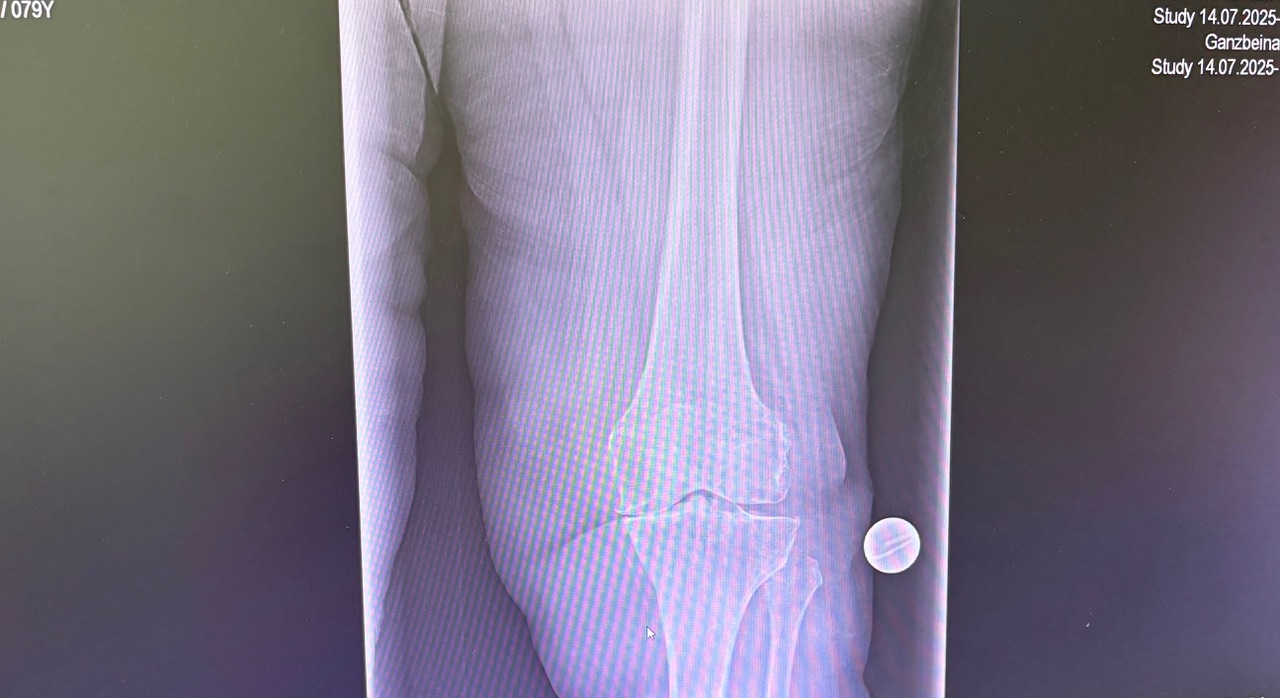

Η ρομποτική αρθροπλαστική γόνατος είναι προηγμένη τεχνική αντικατάστασης γόνατος, όπου ο χειρουργός χρησιμοποιεί ρομποτικό σύστημα υποβοήθησης για εξαιρετικά ακριβή τοποθέτηση των εμφυτευμάτων, βασισμένη στη δική σου ανατομία.

- Προχωρημένη οστεοαρθρίτιδα γόνατος

- Παραμορφώσεις (ραιβό / βλαισό γόνατο)

- Ασθενείς με αυξημένες λειτουργικές απαιτήσεις

- Επανεπεμβάσεις ή δύσκολες ανατομίες